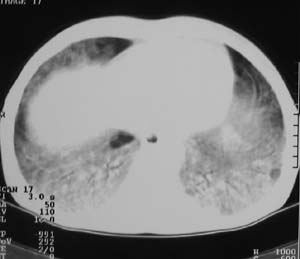

以下是引用zjzjr在2007-9-20 12:29:00的发言:[br]双肺磨玻璃改变,考虑肺水肿.

以下是引用yangzongshan在2007-9-20 18:29:00的发言:[br]两肺毛玻璃样改变,其内可见肺纹理影,无胸腔积液,故考虑肺泡蛋白沉积症

以下是引用276894491在2007-9-20 13:40:00的发言:[br]考虑肺水肿;外源性过敏性肺炎不排除。

以下是引用逸风在2007-9-20 20:45:00的发言:[br]两肺磨玻璃样改变,临床病史短,发热,考虑病毒感染合并右肺代偿性肺气肿.待排肺水肿,病史短,不支持肺泡蛋白沉着症.